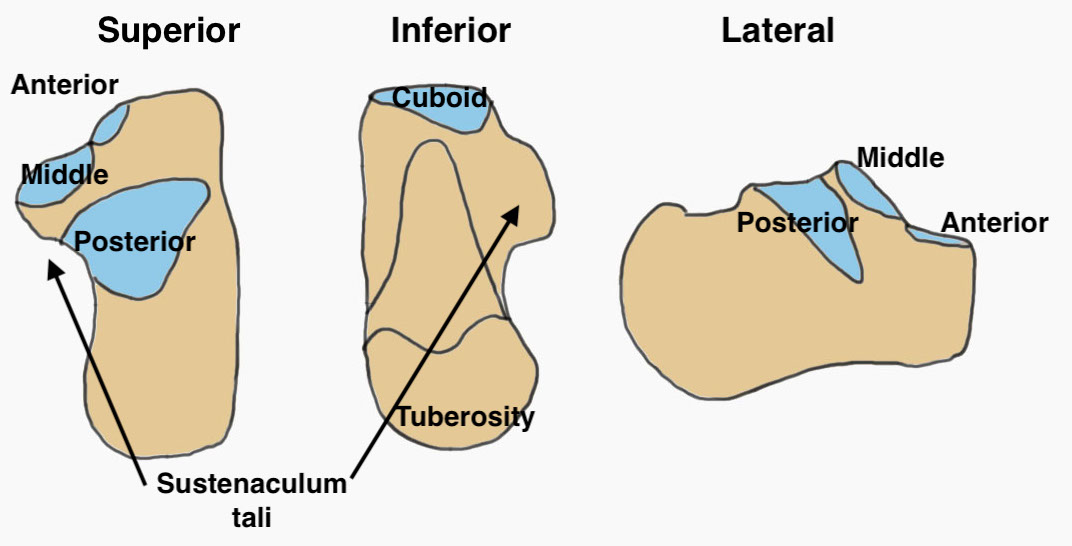

Anatomy

| Facets | Tuberosities | Process |

|---|---|---|

| Posterior facet / subtalar joint | Posterior - tendoachilles | Anterior - calcaneocuboid joint |

| Middle facet (sustenaculum tali) | Medial - adductor hallucis, plantar fascia | |

| Anterior facet | Lateral - abductor digiti minimi |